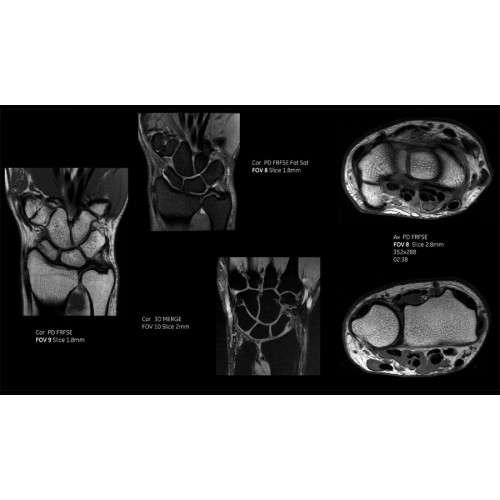

Система SIGNA Pioneer воплощает поразительные достижения в области визуализации. Передовая технология Total Digital Imaging (TDI) позволяет добиться большей четкости изображений и на четверть повысить соотношение сигнал/шум.

TDI построена на трех базовых компонентах:

• Технология Direct Digital Interface (DDI) использует независимый аналого-цифровой преобразователь для оцифровки сигнала от каждого из 97 радиочастотных каналов, что обеспечивает значительное увеличение качества за счет уменьшения фонового шума.

• Технология Digital Micro Switching (DMS) — это следующее поколение технологий радиочастотных катушек, основанное на замене аналоговых схем блокировки сверхбыстрыми микропереключателями (MEMS), что делает возможным быстрое переключение катушек для дальнейшего расширения возможностей визуализации с нулевым TE.

• Технология Digital Surround Technology (DST) — это новая технология объемной оцифровки данных, объединяющая сигналы от каждого элемента катушки. Прекрасное соотношение сигнал/шум и чувствительность поверхностных катушек в сочетании с превосходной однородностью и высокой проникающей способностью встроенной радиочастотной катушки — все это позволяет создавать качественные изображения не только позвоночника, но и всего тела.

Помимо технологии 97 РЧ-каналов, SIGNA Pioneer использует магнит 3.0Т высокой однородности, предназначенный для повышения качества визуализации во всех областях, а также закладывающий прочный фундамент для долгосрочных инвестиций и роста клинических возможностей.